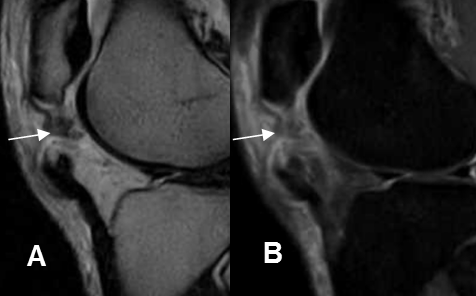

Fig 64 B. Ruptura del tendón del cuadriceps.

A: RM sagital en T2 y B: RM sagital en STIR. Solución de continuidad sobre la inserción del cuadriceps, por ruptura. Hay cambios inflamatorios en los tejidos blandos y bursitis prepatelar.